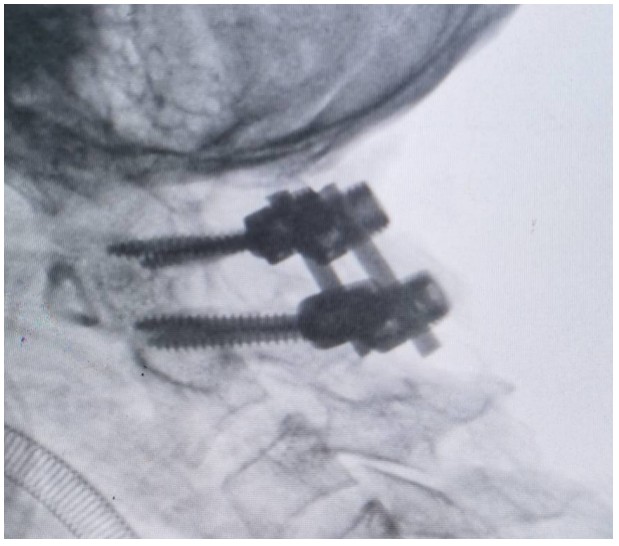

術(shù)中,錢軍博士團(tuán)隊(duì)展現(xiàn)出了非凡的勇氣和精湛的醫(yī)術(shù)。他們精心準(zhǔn)備,與手術(shù)室和麻醉科的同仁們緊密協(xié)作,以專業(yè)的技術(shù)和精確的操作,成功完成了這一高難度的手術(shù)。手術(shù)室外,譚女士的家人焦急等待,當(dāng)手術(shù)成功的消息傳來時(shí),譚女士的家人不禁流下了感激的淚水。

術(shù)后,譚女士在骨科一區(qū)(脊柱外科)醫(yī)護(hù)人員的細(xì)心照料下,逐漸恢復(fù)活力,痛苦得到緩解,頸椎活動也日益靈活。譚女士的家屬對手術(shù)效果感到非常滿意,多次對醫(yī)護(hù)人員的精湛技藝和無私奉獻(xiàn),當(dāng)面表達(dá)出深深的敬意和感激。